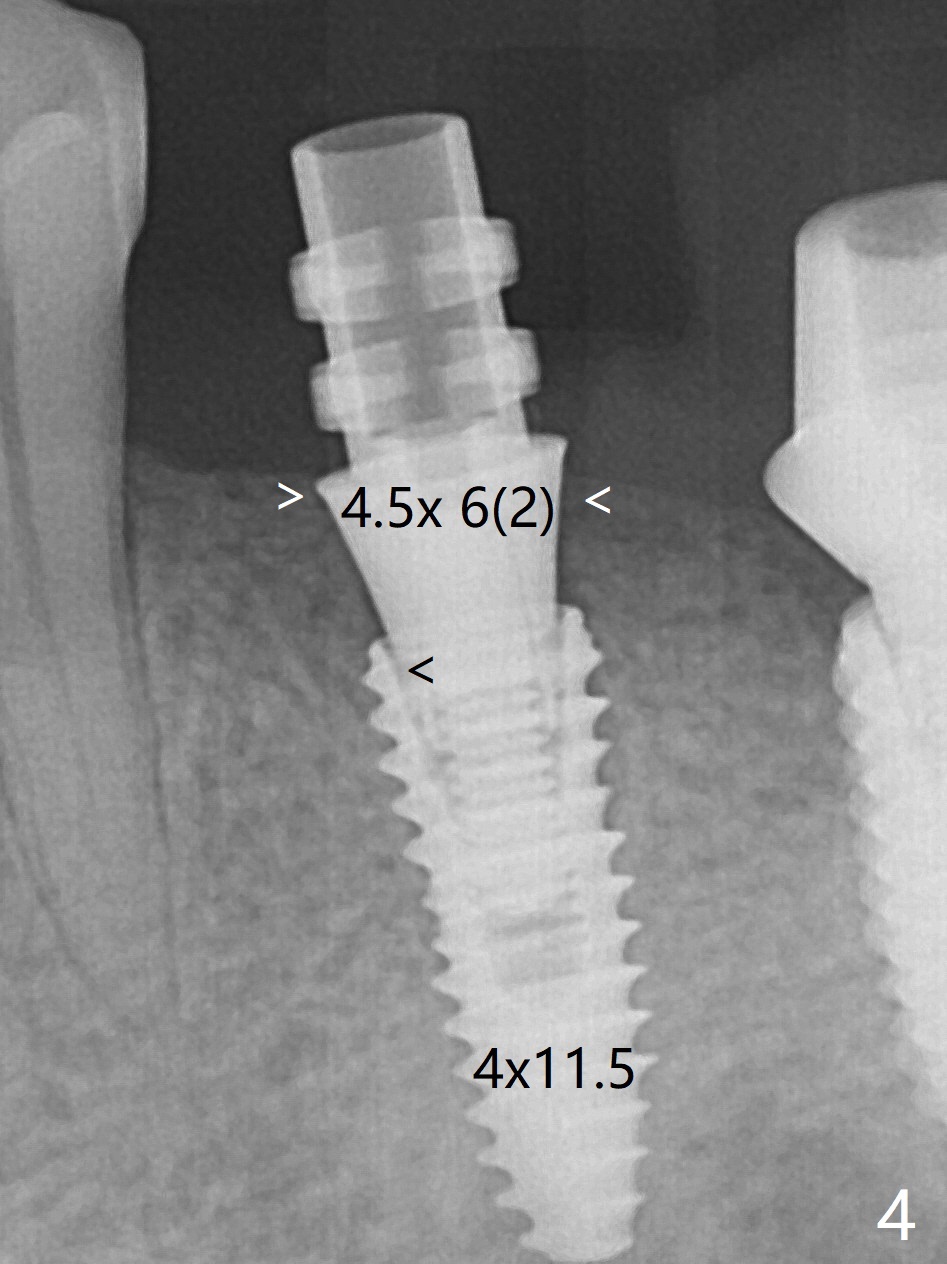

Socket Shield is conducted at #20 (Fig.1-3 *). With placement of a 4x11.5 mm implant equicrestal lingually, a 4.5x6(2) mm temporary abutment is unable to be seated incompletely (Fig.4 black <) because of proximal crestal interference (white arrowheads). After use of a 5.5 mm profile drill, a 5.5x5 mm healing abutment is apparently seated completely (Fig.5). Upon close look, the abutment at #19 is also incompletely seated. In fact #18/19 temporary crowns and #19 abutment are loose. A 6.8x4 mm healing abutment is later placed at #19. Periodontal dressing is applied at #18-20. In fact buccolingual control of osteotomy is not easy with free hand. A smaller implant (e.g., 3.5 mm) may be easier.